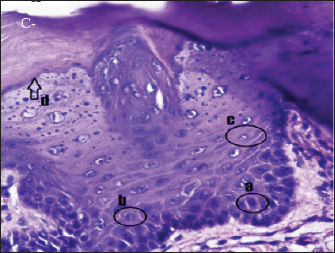

In group (C-), the epithelium of the rat’s tongue had a normal histopathological appearance. There appeared to be a regular epithelial stratification among the cells, with healthy cell turnover in each layer. The base layer consists of hyperchromatic nuclei, while the spinosum layer is composed of irregular polygonal cells. Granulosa has oval-shaped cells. Nucleus and cell organelles vanish, followed by a transition to the corneum layer, demonstrating keratinization development (Fig. 2).

Fig. 2. Histopathologically described the rat tongue epithelium in the negative control group (C-), microscope at ×400. (a) basal layer with a hyperchromatic nucleus and basophilic cytoplasm; (b) spinosum layer with cells of irregular polygonal shape; (c) cells in the granulosum layer with oval cell shape; d. the layer of corneum filled with keratin.